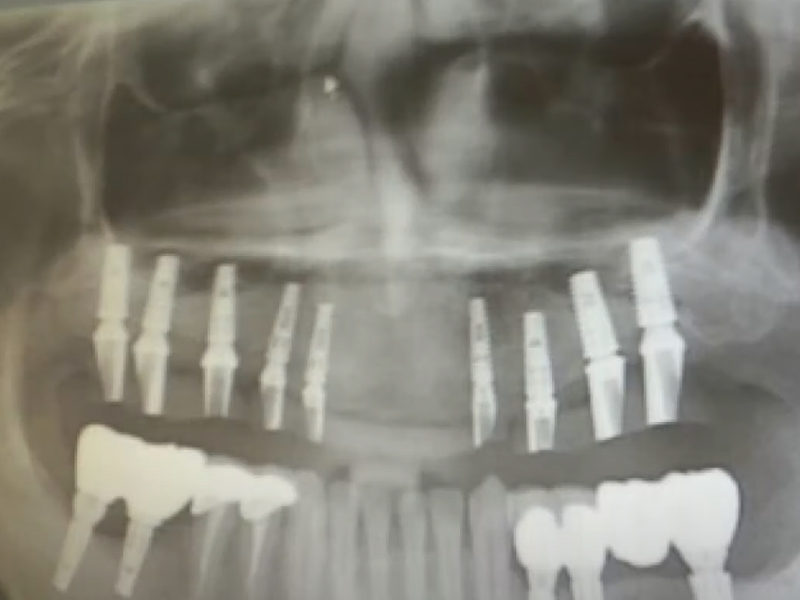

韓國濟州島發生一起牙科手術致死事件,死者為一名61歲的中國男子。根據韓國 KBS 新聞 6 月 13 日的報導,該名男子於今年早些時候在濟州島進行種植牙手術後不幸身亡,目前警方正在調查此案。 死者的家屬表示,事件發生在 2 月 28 日,死者在濟州島一家牙科診所接受了種植牙手術。手術結束後,死者感到劇痛,並在當晚不幸去世。根據法醫的屍檢結果顯示,死因為下頜骨粉碎性骨折引起的出血。 ![]() 接到報警後,濟州警方立即展開調查,認為這可能是業務過失致死案件。警方對涉事牙科診所進行了扣押搜查,以查明該診所是否存在過失行為。 對於此事,涉事牙科診所表示,死者在手術後並無異常,當天便自行回家。診所表示,如果確認有責任,將會承擔相應的責任。 ![]() 目前,案件仍在進一步調查中,警方將根據調查結果決定是否對牙科診所及相關人員進行起訴。 |